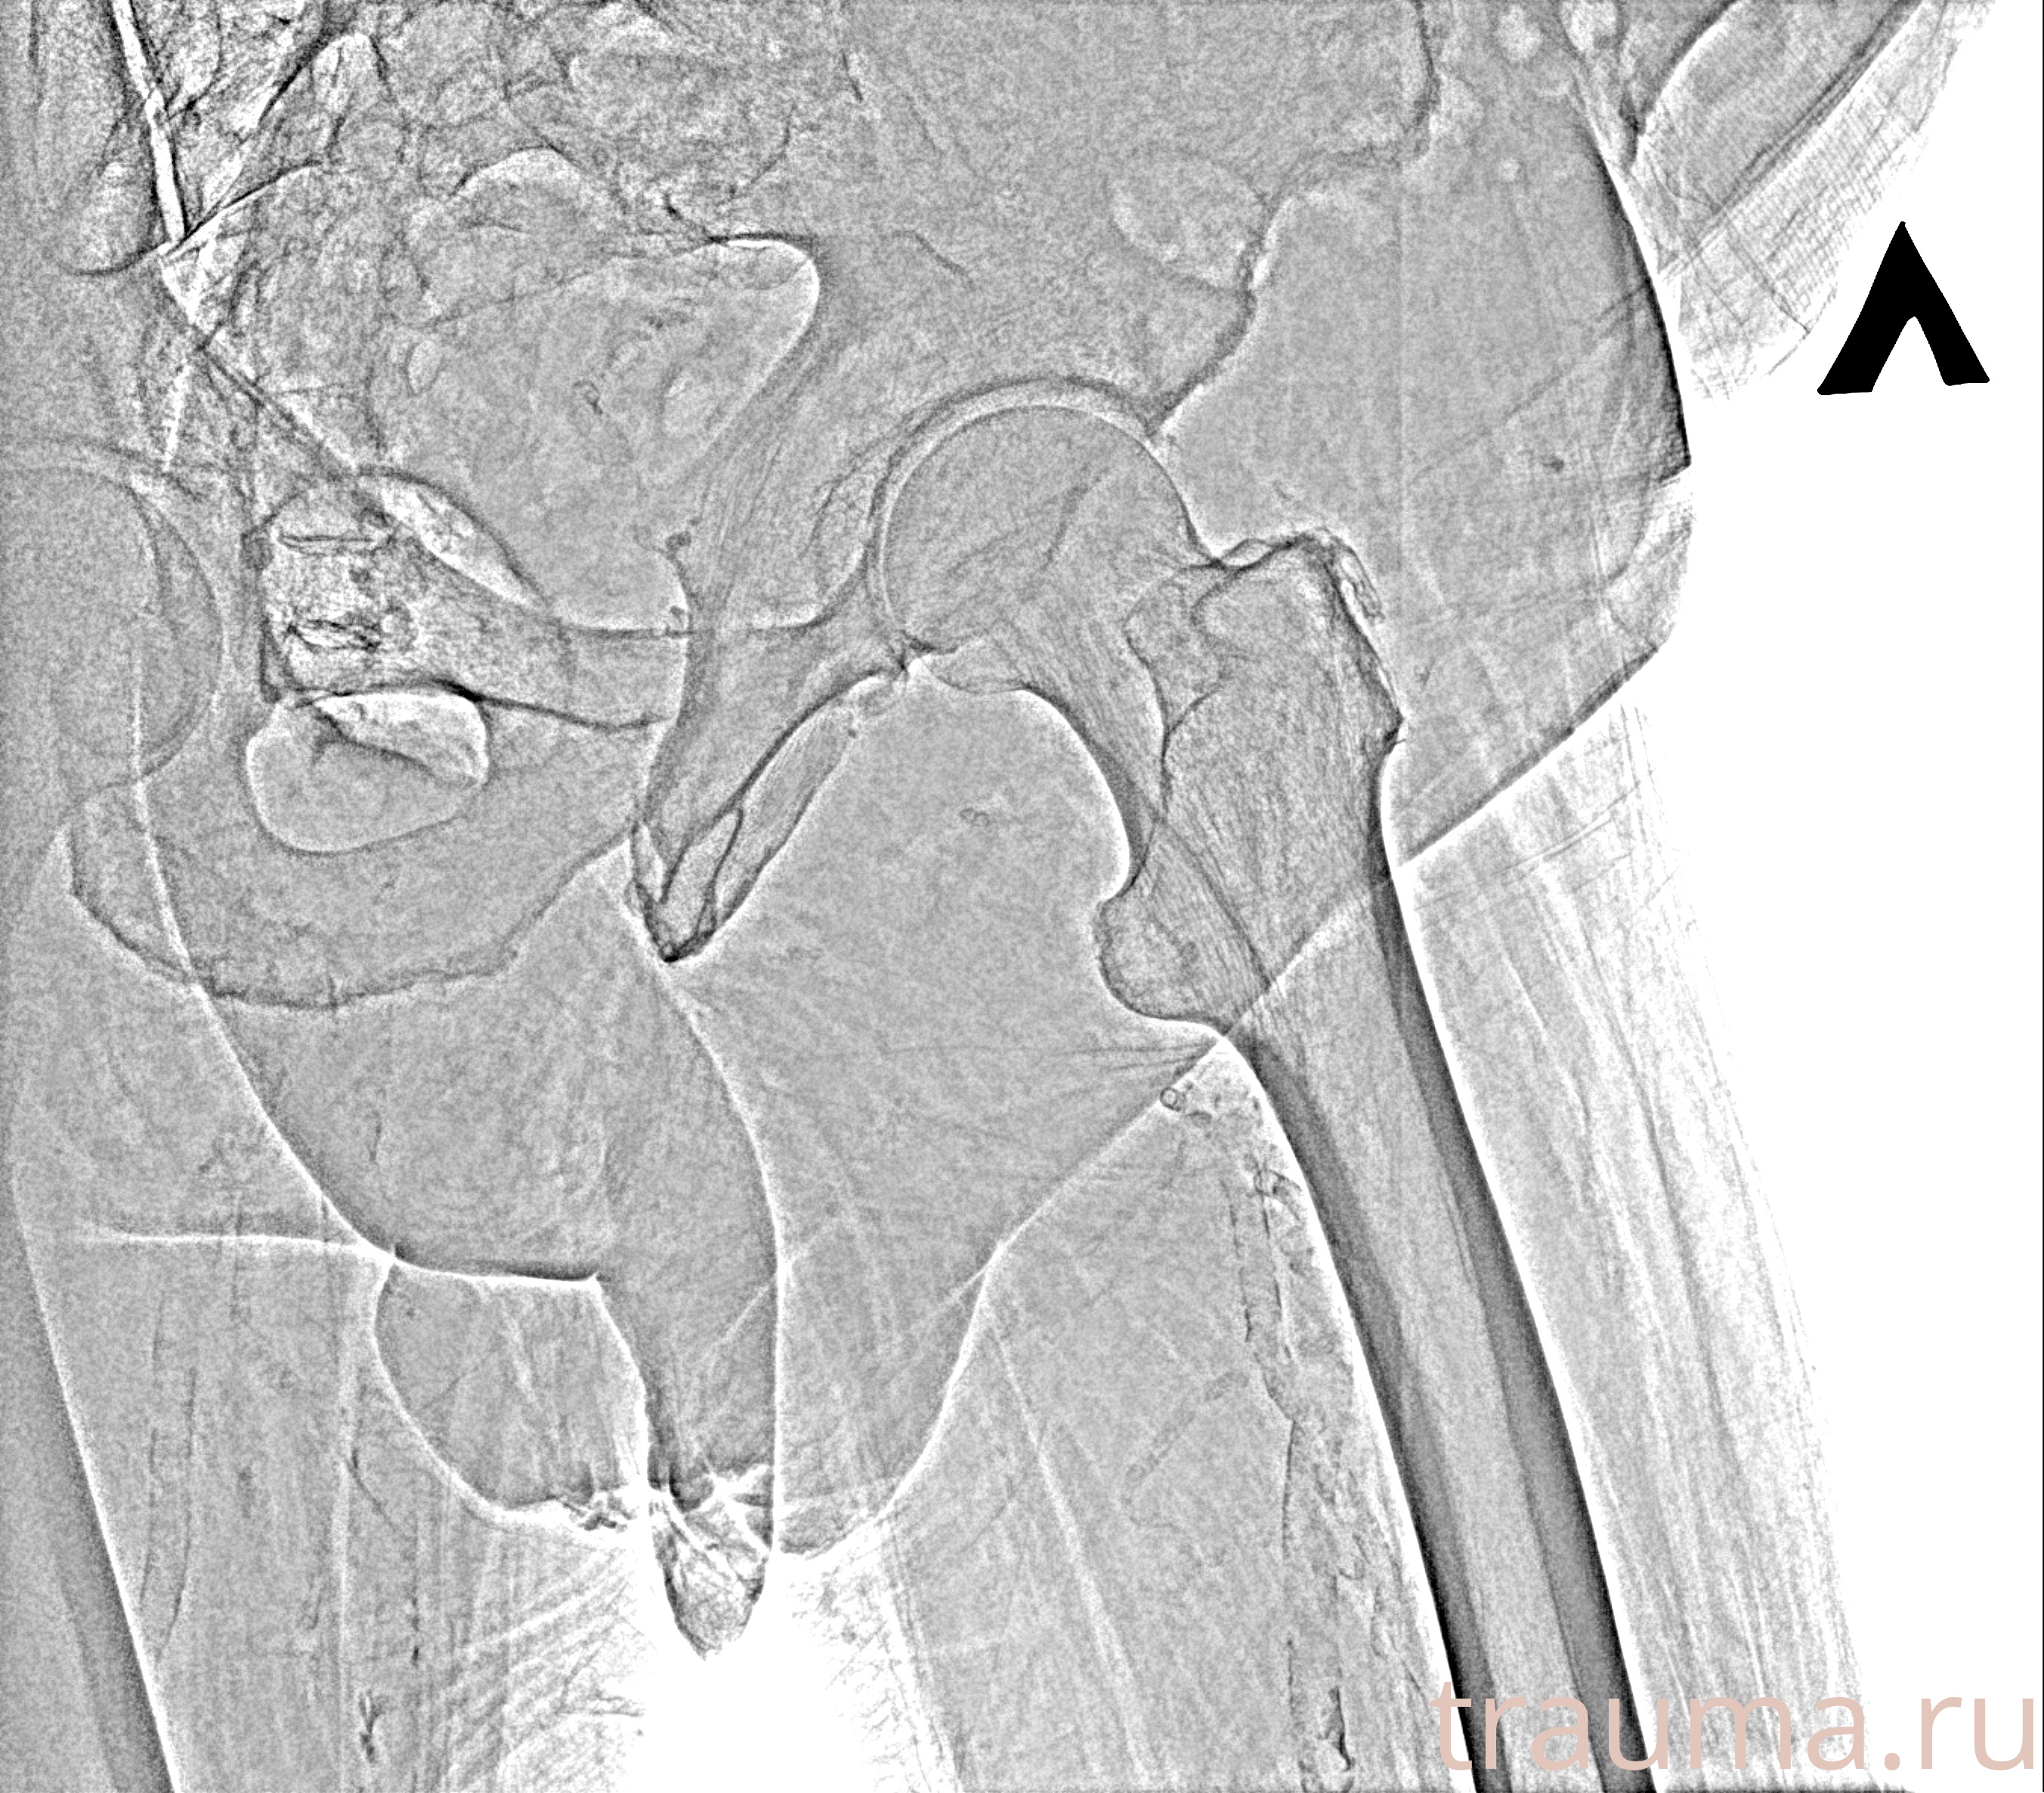

Рентген на дому: по вашему адресу приезжает врач-рентгенолог, травматолог-ортопед с мобильным рентгеновским аппаратом, проводит диагностику травмы или заболевания, делает необходимые рентгенограммы, дает рекомендации по дальнейшему лечению. Получить качественные снимки в домашних условиях возможно благодаря уникальной методике, разработанной МосРентген Центром для института  Склифосовского